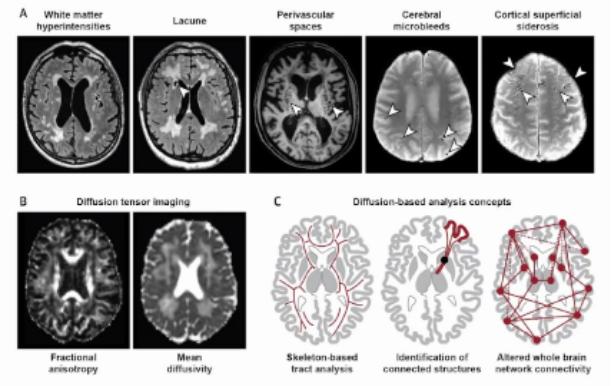

VCI的影像学改变包括皮层下白质病变、腔梗、扩大的血管间隙、脑微出血、皮层表面含铁血黄素沉着、神经元与神经元之间连接的损害等。